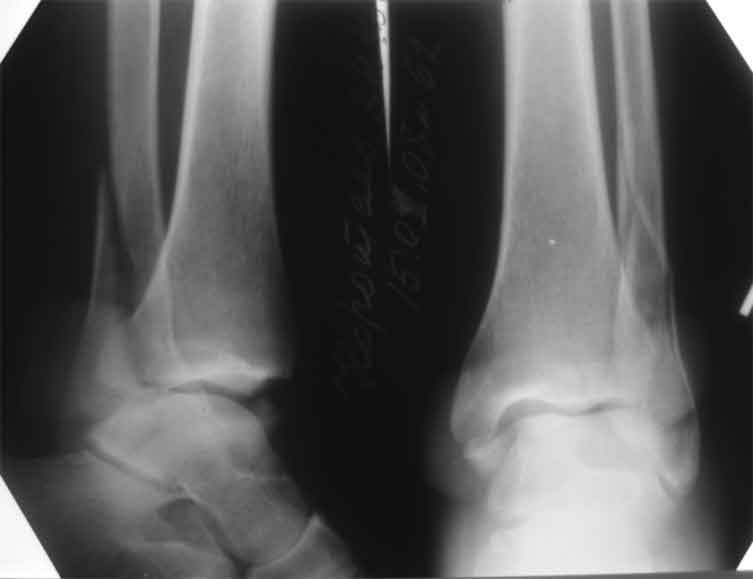

Здесь представлено решение похожей проблемы. Больной в течение года лечился консервативными мерами, и боли в голеностопе были основным показанием к операции.

Проведена обычная стандартная процедура по исправлению неудовлетворительного состояния голеностопного сустава, где кроме удлинения малоберцовой с применением compression tension device за проксимальный конец пластины, проведено замещение трикортикальным графтом из крыла, освобождение синдесмоза и медиальной щели от

фибротических масс с фиксацией.